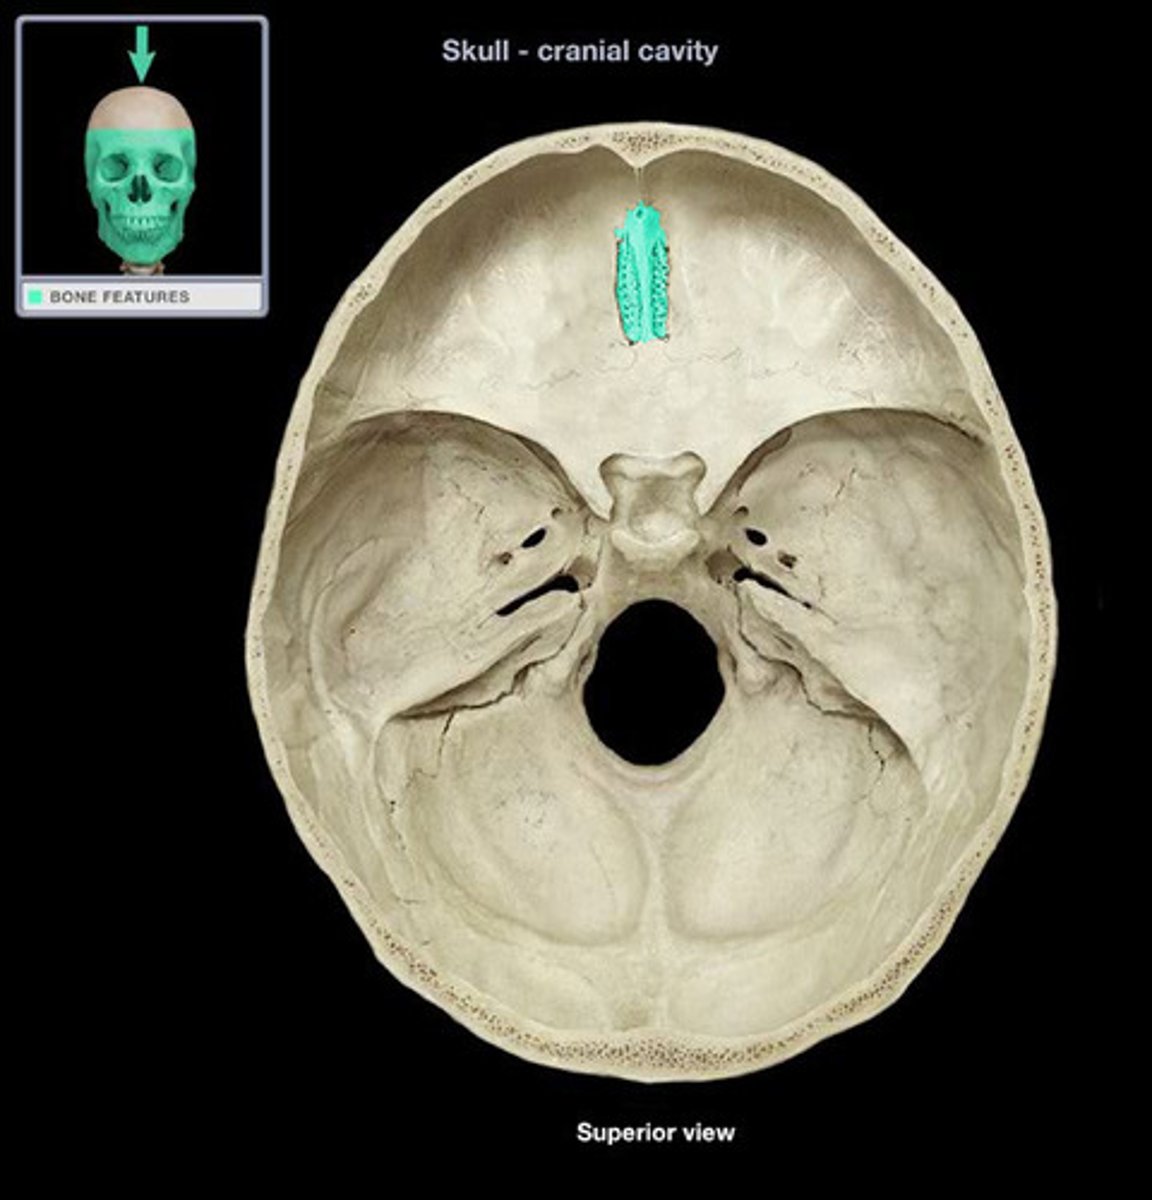

Cribiform Plate